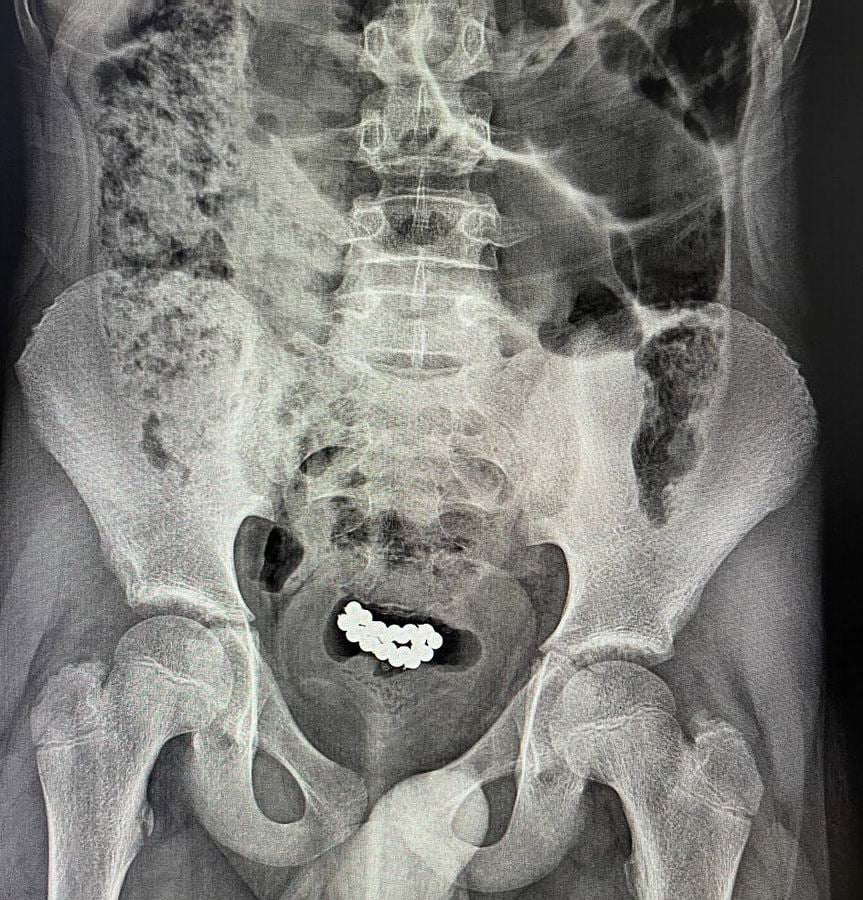

Хотели ярких ощущений: на Волыни у подростков из уретры достали магнитные шарики (фото, видео)

Врачи говорят, что это не первые случаи. С проблемами после экспериментов попадают и юные девушки — к примеру, с инородными предметами в прямой кишке. focus.ua »